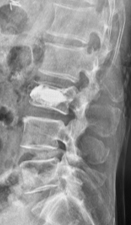

椎体形成術(VP、BKP、VBS)および後方・後側方脊椎固定術

対象となる疾患:脊椎圧迫骨折や転移性脊椎腫瘍による病的骨折など

椎体形成術でセメントや人工骨を注入して、骨折を人工的に接合します。椎体形成術のみでは固定性が弱い場合や骨脆弱性が強い場合には、スクリューなどを用いて脊椎を安定化させます。原則、手術翌日より軟性もしくは硬性のコルセットを装着し、起立・歩行を開始します。

(左)第12胸椎および第1腰椎の骨粗鬆症性椎体骨折を認めます。(中)MRIでは第1腰椎に大きな骨欠損を認め、骨折が難治性で不安定であることを示しています。(右)第1腰椎に椎体形成術を施行し、さらに骨が脆かったため、頭尾側にスクリューを挿入して固定しています。